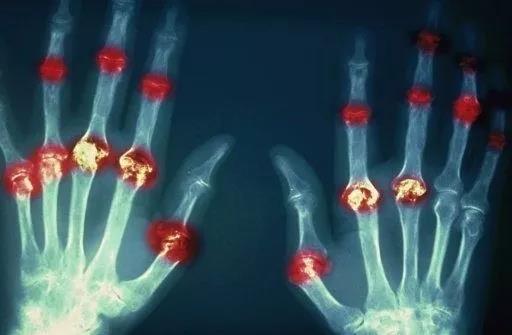

? 類風(fēng)濕關(guān)節(jié)炎

類風(fēng)濕關(guān)節(jié)炎是一種高度致殘的自身免疫性疾病,發(fā)病十年的患者中至少有50%的人失去勞動能力。

類風(fēng)濕關(guān)節(jié)炎©Health Same of Flickr

1977年,Baldwin在用骨髓干細(xì)胞移植治療再生障礙性貧血的過程中,意外發(fā)現(xiàn)患者的類風(fēng)濕關(guān)節(jié)炎得到緩解。

2004年,歐洲骨髓移植和抗風(fēng)濕病聯(lián)盟對60例類風(fēng)濕病關(guān)節(jié)炎移植患者進(jìn)行回顧性分析,這些患者的關(guān)節(jié)破壞都達(dá)到不可修復(fù)程度,生活不能自理,通過干細(xì)胞移植治療后,67%的患者得到明顯緩解。

我國國內(nèi)多家醫(yī)院已開展了干細(xì)胞治療類風(fēng)濕性關(guān)節(jié)炎的臨床研究。首例自體干細(xì)胞移植治療類風(fēng)濕關(guān)節(jié)炎在北京協(xié)和醫(yī)院完成。經(jīng)過5個月隨訪,這些經(jīng)常規(guī)藥物治療失敗且病情發(fā)展迅速的患者,在接受干細(xì)胞移植治療后,癥狀均獲得改善,關(guān)節(jié)腫脹消失,各項檢查指標(biāo)恢復(fù)正常。

解放軍323醫(yī)院2011年的一項臨床研究中,27位患者(對照組)只使用藥物治療;另外153位患者(細(xì)胞治療組)在藥物治療的基礎(chǔ)上進(jìn)行臍帶間充質(zhì)干細(xì)胞輸注。結(jié)果顯示,治療組DAS28、HAQ 評分、ACR20較對照組下降明顯(分值越低,療效越好),Th1/Th2趨于平衡、Treg升高與臨床實驗指標(biāo)及癥狀的緩解直接相關(guān)。